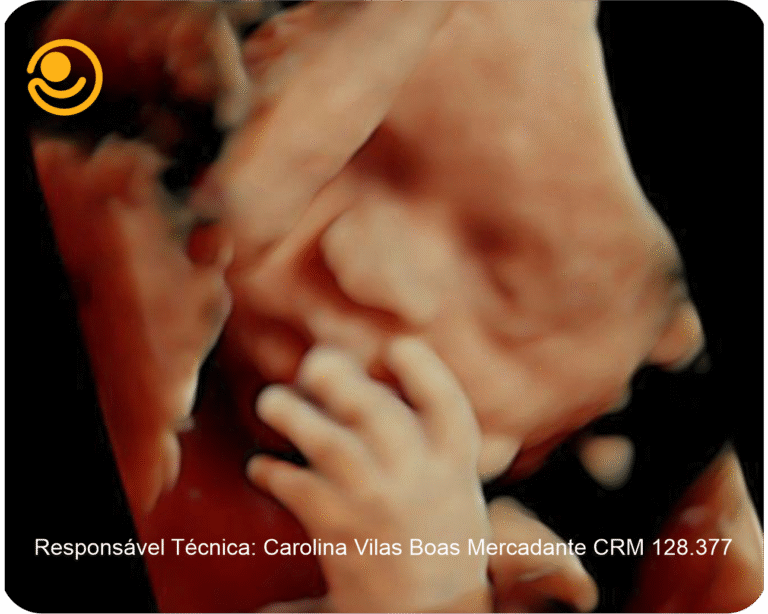

3D / 4D Live – Maior realismo nas imagens e mais precisão nos diagnósticos.

Imagens 3D / 4D

✓ Ultrassonografia 3D/ 4D com imagem em HD